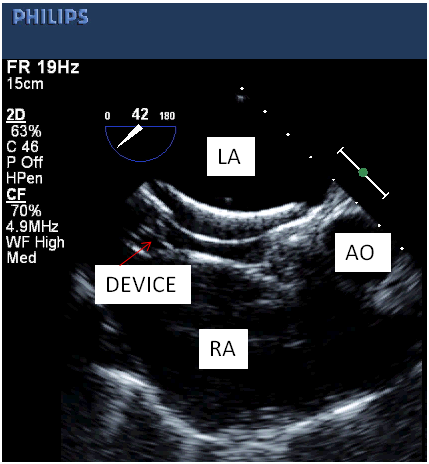

The patients were divided into two groups depending on echocardiographic guidance during device deployment. In group A TTE while in group B TEE was used as guiding tool for device deployment during percutaneous closure of secundum ASD. All patients were called a day before the procedure and clinical examination with complete blood count and chest X-Ray was done to rule out infection. An approval from ethical committee of the institution as well as written consent was taken before the procedure. The procedure was carried out with local or general anaesthesia. The device was deployed in a standard fashion under fluoroscopic and echocardiographic guidance. In some patients additional techniques including balloon assistance, dialator support or pull through were required for device deployment. The device position and residual leak was confirmed with TTE or TEE before the release of device (Figure 1 & 2). All patients were given I/V heparin 100u/kg and first dose of antibiotics (ceftriaxone) 50mg/kg during the procedure followed by two additional doses. The patients were discharged after 24 hours and TTE was performed at the time of discharge. The patients were advised aspirin 5mg/kg for six months and regular follow ups at 1,3 & 6months.

Figure 1 Showing well placed device under TEE guidance.